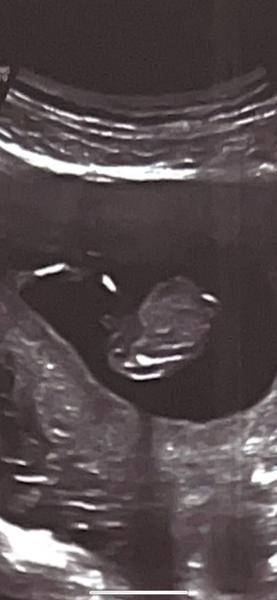

Tipnete si pohlaví z obrázku? Holka nebo kluk?

Ahojte, na 1. screeningu nám nechtěl říct pohlaví, jen z principu že to neříká 😄 ale natočený byl pěkně, všechno nám ukázal. Zkusíte tipnout ? Jednu fotku máme zespod a jednu z boku přímo na pohlaví. My jsme mu svůj tip řekli ale na to nám jen odpověděl bez komentáře 😄🙈

Já tam nic nevidím, ani na předposlední fotce bych kluka netipovala, nemyslím, že je to záběr mezi nožičkama a vůbec se nedivím, že nechtějí říkat pohlaví. V 17. týdnu nám řekli, že to bude holka a ve 20. týdnu se omlouvali celé naší rodině, protože to byl kluk jako buk. Tak ještě chvilku vydržte.